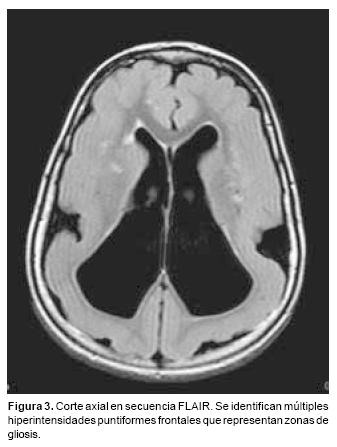

Paciente masculino de 3 años de edad, producto de la segunda gestación, obtenido por cesárea a las 30 semanas de embarazo. Cursó con crisis convulsivas tónico clónicas de difícil manejo desde los 8 meses de edad, así como con retraso psicomotor. Se realizó resonancia magnética (RM) de cráneo con los siguientes hallazgos: en la secuencia T2 en plano axial, a nivel de los ventrículos laterales se observó un engrosamiento generalizado de la corteza cerebral en ambos hemisferios, asociado a ausencia de surcos cerebrales normales que le dio un aspecto "liso" al cerebro (Figura 1). La cisura de Silvio en ambos lados se encontró amplia y poco profunda lo que le confirió un aspecto en figura de "8". En la imagen sagital en secuencia FLAIR (Fluid Attenuated Inversion Recovery) la línea media el cuerpo calloso se observó adelgazado de forma generalizada (Figura 2). En las adquisiciones axiales en secuencia FLAIR se identificaron imágenes puntiformes, hiperintensas, confluentes de localización subcortical en ambos hemisferios, de predominio frontal compatibles con zonas de gliosis (Figura 3).